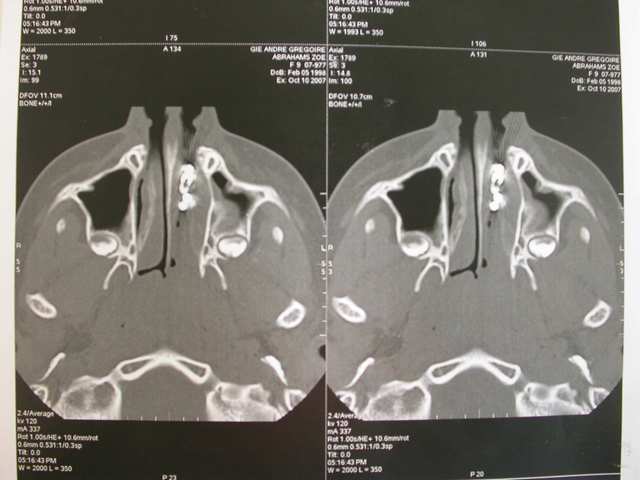

Je décide donc de faire réaliser un scanner et là c’est nouveau pour vous.

Une fois le scanner réalisé, je vois bien qu’il s’agit d’un objet composé de boules et l’adresse illico à son orl. Il la reçoit dans la foulée, et au vu du scanner, se refuse d’intervenir de peur de renvoyer plus loin l’objet. A son tour, il l’adresse à un hopital spécialisé enfants (Robert Debré). Au service ORL, ils tentent de retirer l’objet avec une pince (comme Dr House le faisait dans un épisode) et rien de neuf, aucune progression.

L’ORL qui s’occupe de Zoe est têtu et tente un dernier coup, en branchant une aspiration chirurgicale hyperpuissante et en couplant l’action de celle-ci avec la pince de House. Et petit à petit, il arrive à sortir cette fameuse chainette. Le tout sans anesthésie.

La maman m’a rapporté toutes les pieces quelques jours après, et c’est à ce moment là, qu’elle m’a confié que cela faisait plusieurs années, que Zoe présentait une espéce de sinusite et d’écoulement nasal unilatéral. Elle avait juste oublié d’en parler à son médecin, son ORL, ou même à moi lorsque je l’ai questionné.